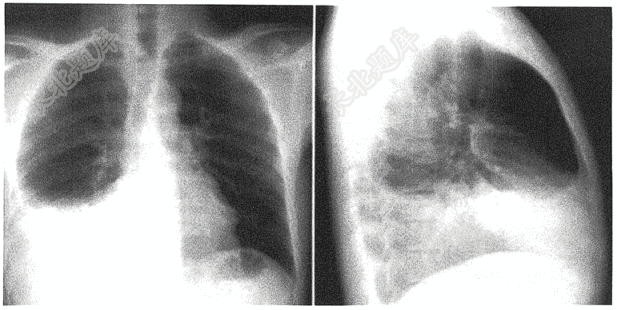

- 单项选择题男性,51岁( )

A、右下肺炎症

B、左下肺炎症

C、右侧胸腔积液

D、左侧胸腔积液

E、右下肺癌